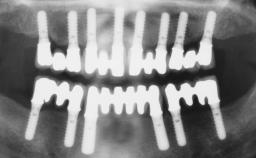

Conventional Loading of Six Implants in the Mandible and Final Restoration with a Full-Arch Metal-Ceramic FDP

# of Implants 6

Type of Implants One-Piece

Prosthesis Type FDP

Prosthodontic SAC classification

SAC Level Complex

Defining Characteristics Fully edentulous lower jaw to be rehabilitated with an implant-borne fixed dental prosthesis

Loading Protocol Conventional/early

Retention Screw-retained, with 4 or more splinted implants Screw-retained, with 4 or more splinted implants

Inter-Arch Distance Adequate

Bruxism Absent